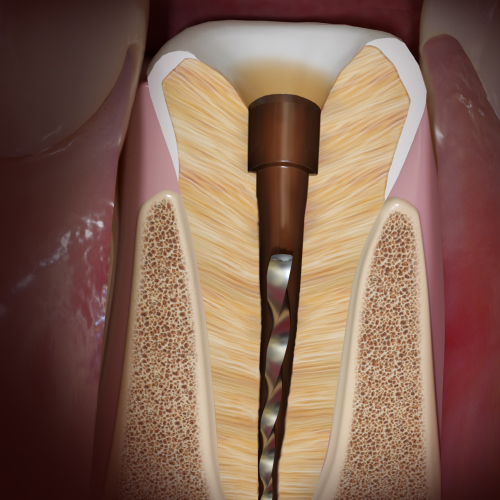

New Directions in Endodontics

Tuesday, April 2, 2024

This Compendium eBook features a continuing education (CE) article on the management of endodontic flare-ups. This eBook also includes an article on intentional replantation as a predictable and cost-effective option for preserving a natural tooth and as a favorable alternative to conventio...

One-Day Endo-Restorative Treatment: The Integration of Advanced Technology and a Single-Visit Workflow for General Dental Practitioners

Scott Sayre, DDS, MBA, MAS

Monday, February 26, 2024

This Compendium eBook offers a continuing education (CE) article that explores the integration of technology as part of a single-visit workflow for root canal therapy that can be implemented by the general dentist. Download to earn 2 complimentary CEU now!

Endodontic Pathways

Friday, September 29, 2023

This Compendium eBook features a continuing education (CE) article on the prevention and management of endodontic rotary nick-titanium (NiTi) file breakage. An article describing advances in endodontic care and pain management is also included in this eBook. Download to earn 2 complimentary...

Endodontic Updates

Wednesday, March 22, 2023

This Compendium eBook offers a continuing education (CE) article on unseparated fractures and their diagnostic complexities. This eBook also includes a case report article on the use of cone-beam computed tomography for the analysis of atypical root canal anatomy. Download to earn 2 FREE CE...

Endodontic Advances

Friday, October 21, 2022

This Compendium eBook offers a continuing education (CE) article that examines the most recent guidelines of the American Association of Endodontists and the American Dental Association regarding the prescription of antibiotics, and outlines the best choices for antibiotic treatment for bot...

Breakthroughs in Endodontics

Monday, October 4, 2021

This Compendium eBook offers a continuing education (CE) article on the critical decision-making process involved in determining whether to restore or replace compromised maxillary anterior teeth, with an emphasis on the importance of timely treatment decisions and their criteria. In addit...

Developments in Endodontics

Wednesday, July 14, 2021

This Compendium eBook offers a continuing education (CE) article on mineral trioxide aggregate (MTA) and its composition, clinical applications, and research findings. This eBook also includes a case report on the use of conebeam computed tomography (CBCT) to diagnose anatomical disparities...

Advancements in Endodontics

Monday, August 31, 2020

This Compendium eBook consists of a continuing education (CE) article on ridge preservation strategies in children who experience anterior tooth trauma. A second article is a case report that uses cone-beam computed tomography (CBCT) for diagnosis, evaluation, and endodontic management of a...

Innovations in Endodontics

Friday, May 8, 2020

This Compendium eBook offers a continuing education (CE) article that features the importance of proper pretreatment diagnosis and the identification of etiology in endodontic retreatment. A second article provides an up-to-date report on comprehensive endodontic pain management.

Innovative Technologies Within Endodontic Practices to Improve Treatment Outcomes: The Importance of Patient Referral

Wednesday, November 20, 2019

This Compendium eBook features a continuing education (CE) article on advancements in technology that have provided a better understanding of the complex anatomies found in root canal systems.

Spotlight on Endodontics

Thursday, August 1, 2019

This Compendium eBook includes a CE article that describes techniques for placement of posts. The second article presents a case report on a multidisciplinary approach to the management of a mandibular first molar.

Today's Trends in Endodontics

Wednesday, February 6, 2019

The relationship between endodontics and restoration is explored in two continuing education (CE) articles presented in this special Compendium eBook. The first article explains the importance of obtaining a pulpal and periradicular diagnosis before restorative treatment. The second discuss...

Current Topics in Endodontics

Monday, September 24, 2018

This special Compendium eBook presents two articles on topics in endodontics. The first article, a continuing education course with a quiz for 2 credits, examines various steps of endodontic treatment and how, from a restorative standpoint, treatment can be improved for better long-term predictabili...

Advances in Endodontics

Wednesday, February 14, 2018

This eBook provides two continuing education articles on endodontics topics. The first article reviews solutions to the problem of endodontic rotary file breakage. In the second article, the authors examine mineral trioxide aggregate (MTA), a material that has become vital in endodontic dentistry.

Updates in Endodontics

Wednesday, December 6, 2017

This special Compendium eBook provides two CE articles to increase practitioners' knowledge of endodontics topics. The first article describes the vital role that irrigation plays in successful endodontic treatment. The second article addresses the complexity of the pulp root canal and the difficult...

Endodontics

Monday, April 17, 2017

This special Compendium eBook discusses how local anesthesia can be used to provide pain-free endodontic therapy. Also, a successful pulp capping procedure is described along with stepwise excavation associated with restorative treatment for deep caries lesions. Download today and earn 4 FREE CEU!

Clinical eBook Series: Endodontics

Thursday, April 21, 2016

With more than 24 million endodontic procedures being performed in the United States annually, endodontists are discovering new methods and technologies to treat their patients effectively, quickly, and comfortably. This eBook examines topics aimed at helping endodontists master their craft.